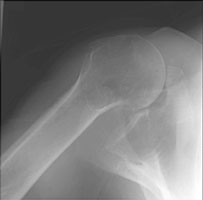

Anterior Dislocation (Humerus)

Anterior shoulder dislocations account for 97 % of shoulder dislocations. They are usually due to indirect force, such as from abduction and internal rotation. The humeral head lies inferior and medial to the glenoid. As the dislocation occurs, the Hill-Sachs lesion and the Bankart fracture may occur as a result of the humerus striking the inferior rim of the glenoid. Labral (non-osseous) injuries may also result, leading to recurrent dislocations.

- Click on the image for a larger versionAAP radiograph of the shoulder. This shows marked overlap of the humeral head and the glenoid.